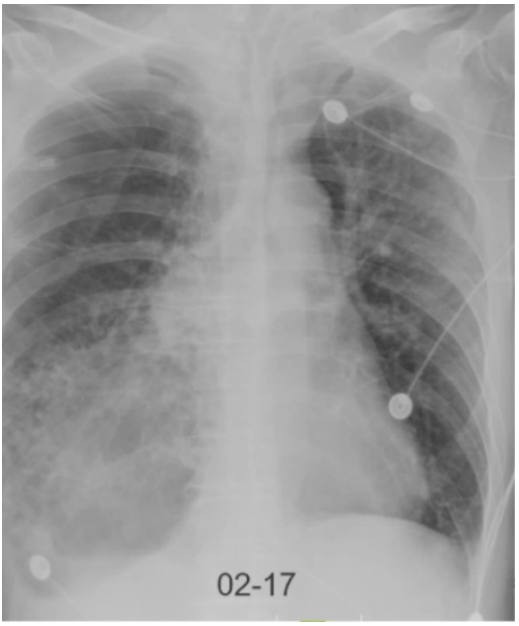

床旁胸片示:右侧弧形向内的透亮影【考虑可能是肺大疱的位置】,两肺散在模糊影,左侧少量气胸已显示不清,无明显右气侧气胸迹象(图2)。